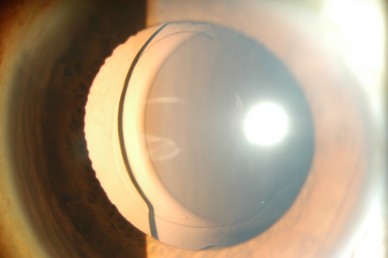

白内障手術によって固定された人工のレンズ(眼内レンズ)が本来の位置からずれてしまう状態のことです。

白内障手術後時間が経過すると、まれに(100人中1人程度)手術で固定した眼内レンズがずれたり外れたりすることがあります。周りの組織が加齢とともに弱くなることが原因です。その他に打撲などの外傷、強い近視、ぶどう膜炎などの炎症、網膜硝子体手術など他の手術の既往があるとレンズを支えている組織が弱くなることがあります。症状として、視力低下、二重に見えることや見え方が変わる(目の中でずれたレンズが動く)ことがあります。

ずれたレンズは自然に元の位置に戻ることはありません。眼内レンズを摘出して新しい眼内レンズを固定する手術が必要になります。この手術は通常の白内障手術よりやや難しく、時間がかかりますが、多くの場合手術後の経過は良好です。